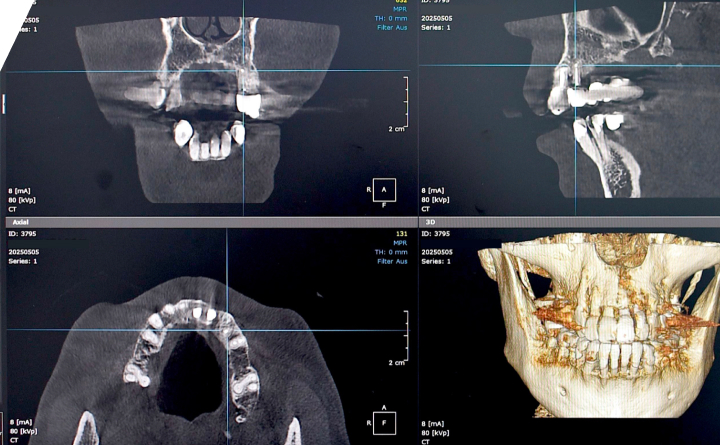

In unserer Praxis in Wien setzen wir auf hochmoderne 3D-Röntgentechnologie in Kombination mit einem Dentalmikroskop, um eine präzise, sichere und schonende Diagnose zu ermöglichen. Diese Technik ist ein unverzichtbarer Bestandteil jeder ästhetischen Behandlung – von der einfachen Zahnfüllung bis hin zu komplexen Eingriffen wie Veneers und Zahn Implantat.

Dank des digitalen 3D-Röntgens (DVT – Digitale Volumentomographie) erhalten wir ein detailliertes, dreidimensionales Bild der Zahn- und Kieferstruktur. So können wir Erkrankungen frühzeitig erkennen, Nervenverläufe exakt darstellen und Behandlungen wie Implantationen oder Wurzelbehandlungen exakt planen – völlig schmerzfrei und mit minimaler Strahlenbelastung.

Vorteile des 3D-Röntgens:

– Höchste Präzision bei Diagnostik und Behandlung

- Verbesserte Sicherheit bei chirurgischen Eingriffen

- Exakte Planung für Veneers und Ästhetik

- Schonende, zeitsparende Verfahren

- Ideal für komplexe Zahnfüllungen und